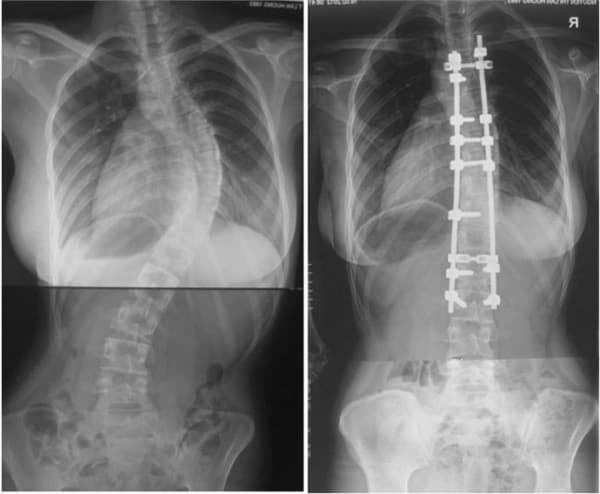

- Cong vẹo cột sống cần được chỉ định phẫu thuật

– Biến dạng cột sống – vẹo cột sống, gù vẹo cột sống, viêm cột sống dính khớp;